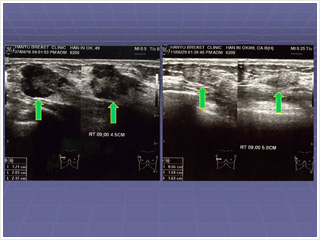

La Diaconesse Inok Han avait une masse palpable dans le sein droit lors de l’hiver 2006. On a diagnostiqué un cancer du sein par biopsie en Avril 2007 et le résultat a montré qu’elle avait un carcinome canalaire invasif de 2 ,17 cm. Le médecin a recommandé une opération, mais elle voulait être guérie seulement par la foi. Et ainsi elle n’a reçu aucun traitement médical, ni subi aucune opération. Comme le temps passait, elle souffrait de sévères douleurs dans le sein droit et de douleurs lancinantes dans le bras droit. En écoutant la parole de Dieu chaque semaine, elle a réalisé que ses péchés étaient graves et elle s’est fermement repentie de ses péchés d’arrogance, de haine, de ressentiment, de sentiments de malaise, de blâmer les autres et d’adorer des idoles. Elle a essayé fortement d’atteindre le cœur de bonté que Dieu voulait comme cela est relaté dans la Bible. En 2009, elle a prié avec une plus grande foi après avoir entendu du Dr. Jaerock Lee en rêve que la lumière de la puissance est venue en elle.

Le 10 Juin 2011, à la réunion spéciale de guérisons divines, elle a reçu la prière du Dr. Jaerock Lee. La masse palpable dans le sein gauche s’est réduite petit à petit. Elle ne ressentait plus de douleurs dans le sein droit et le bras droit. Le 29 Juin 2011, elle a été réexaminée dans le même hôpital. Son cancer du sein avait entièrement disparu. Mais un nodule homogène de petite taille a été détecté dans le diagnostic.

Pour faire cette présentation à la conférence, je lui ai demandé d’avoir un diagnostic adéquat. Elle donc subi une biopsie et le résultat a montré qu’il n’y avait aucune cellule cancéreuse et qu’elle avait des fibroses qu’a une femme ordinaire en bonne santé. J’ai pu voir que le cancer du sein était entièrement guéri.

Le Dr. Zipporah Ngumi, présidente du Comité d’Organisation a dit après la présentation du cas, «Il était plus merveilleux de voir le matériel radiologique correct et la biopsie avant et après la guérison, présentés par le radiologiste.» La présentation a été bien reçue par de nombreux médecins parce qu’ils n’avaient jamais vu de cancer du sein guéri sans traitement médical et ils n’avaient même jamais lu de dissertation sur le sujet.

1. La Diaconesse Inok Han qui a été guérie de cancer du sein. 2. Un nodule de 2cm a disparu 3. Ultrasonographie: un nodule homogène de la taille de 2,17cm a disparu